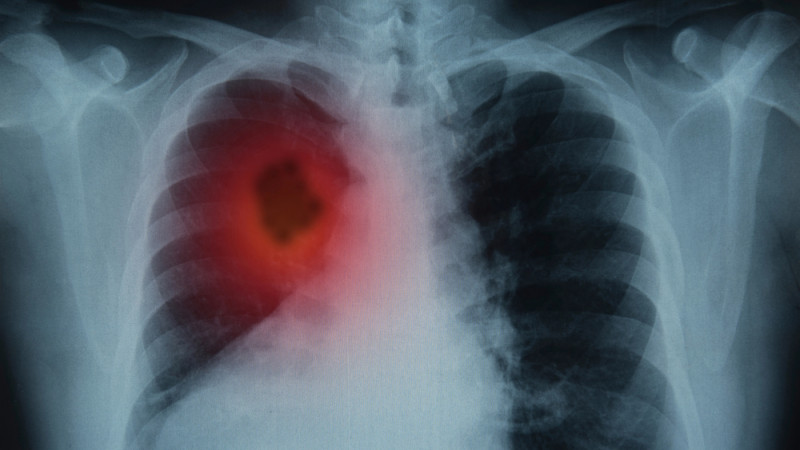

Врач назвал эффективный способ выявления рака легкого

Рак легкого является одним из наиболее агрессивных онкологических заболеваний, но для его диагностики существует действенный метод - НДКТ-скрининг,